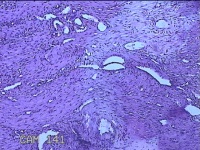

宫腔粘连带

性别

女

年龄

44岁

临床诊断

稽留流产 宫颈炎 宫腔粘连? 宫颈息肉

一般病史

停经1月,发现胚胎停育半天。

标本名称

大体所见

灰白暗红色不规则碎组织1.3x1.2x0.3cm一堆。

图1